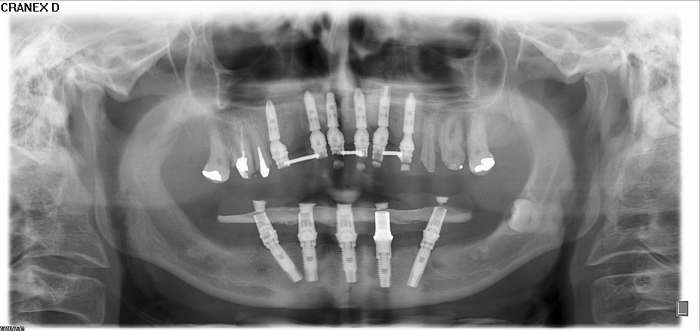

Raio - x Próteses Definitivas em Outubro de 2016  - Clínica Cliniface

Raio - x Próteses Definitivas em Outubro de 2016